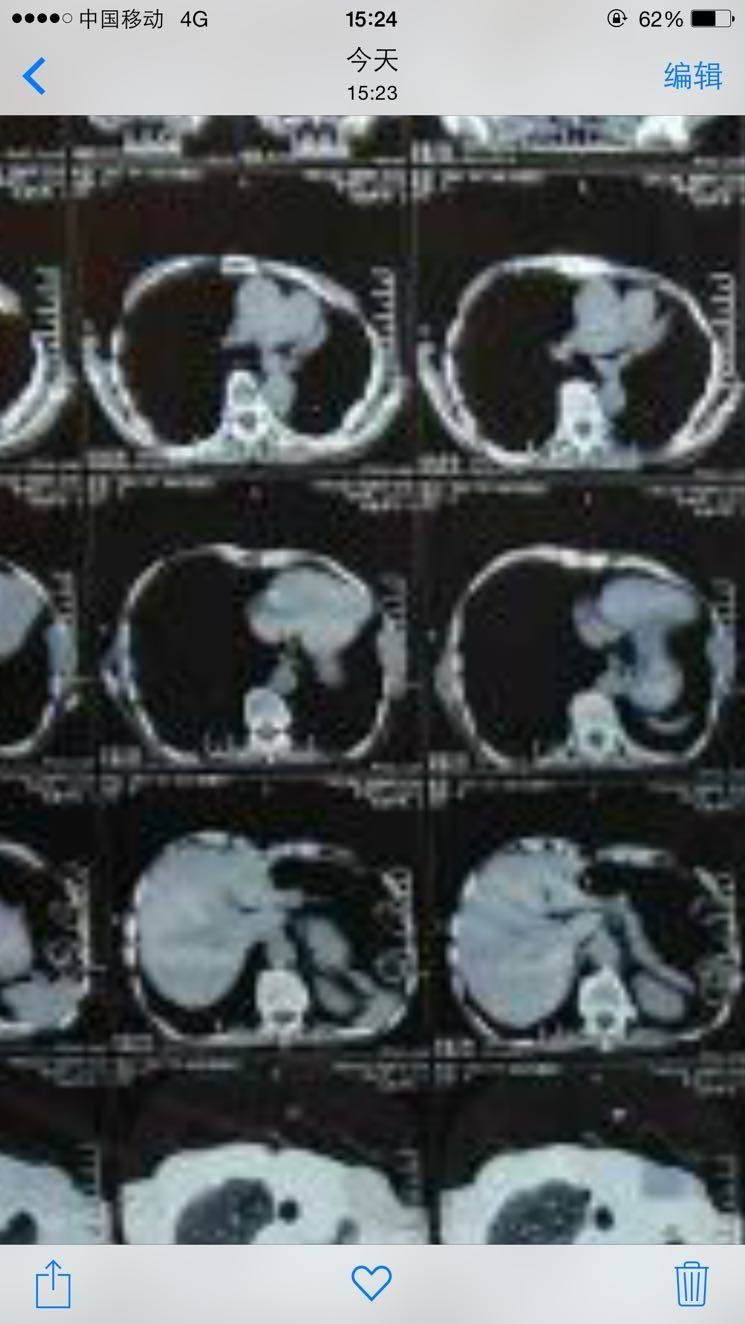

陈波医生注意片子右侧边缘隆起的部分就是转移到胸膜的和侵犯肋骨

陈波医生直视图片右侧,也就是人体左侧,明显有一块隆起突出的弧形凸出

陈波医生不折腾做了,你发给我的6月的CT可以看得出有侵犯胸膜和对应的肋骨